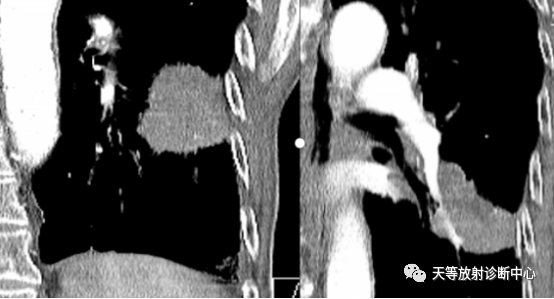

▲周围型肺癌:肿块类圆形,生长较快,具有向肺门方向生长趋势(与支气管匍匐征类似)

明显强化,局部包绕侵犯血管。